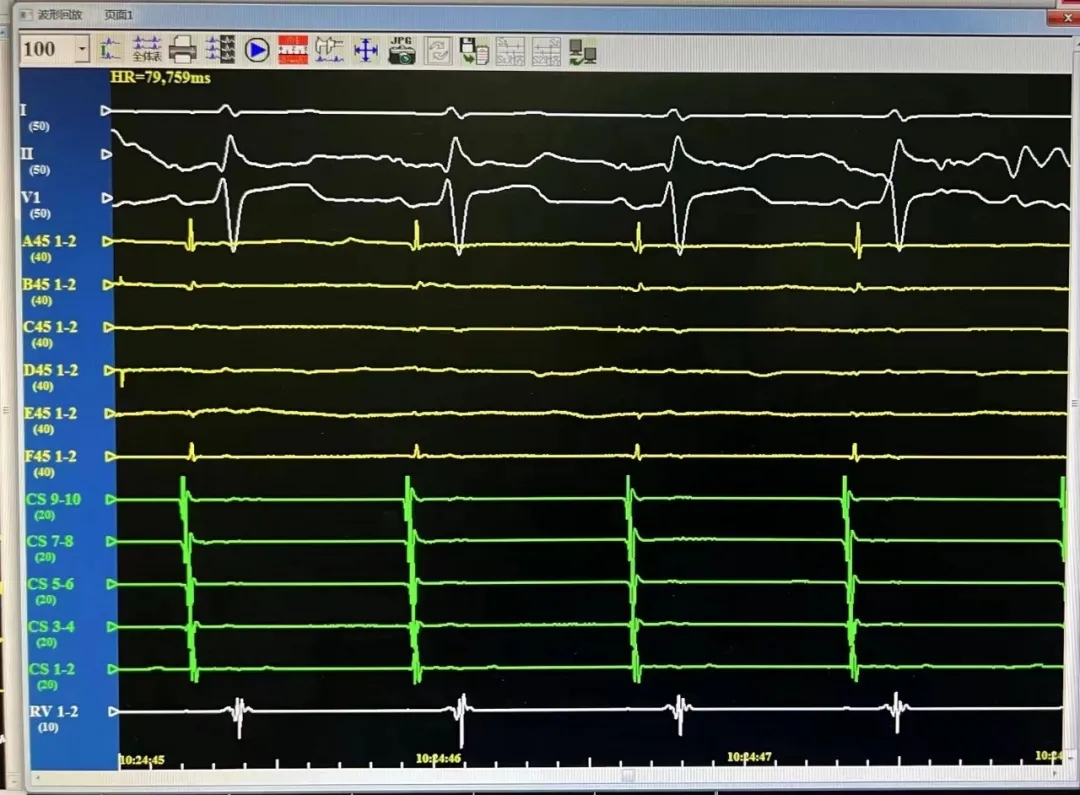

术中均直接采用CardiPulse®脉冲电场消融自身标测电极进行了电位标测,消融即刻及消融结束后四根肺静脉电位消失并双向传导阻滞,结果满意。

LSPV,消融前后电位。消融后电位即刻消失。

LIPV,消融前后电位。消融后电位即刻消失。

RSPV,消融前后电位。消融后电位即刻消失。

RIPV,消融前后电位。消融后电位即刻消失。

消融完成后,分别进行四支肺静脉电位验证。电位无恢复,证明传入阻滞。起搏电极,无法带起心房证明传出阻滞。